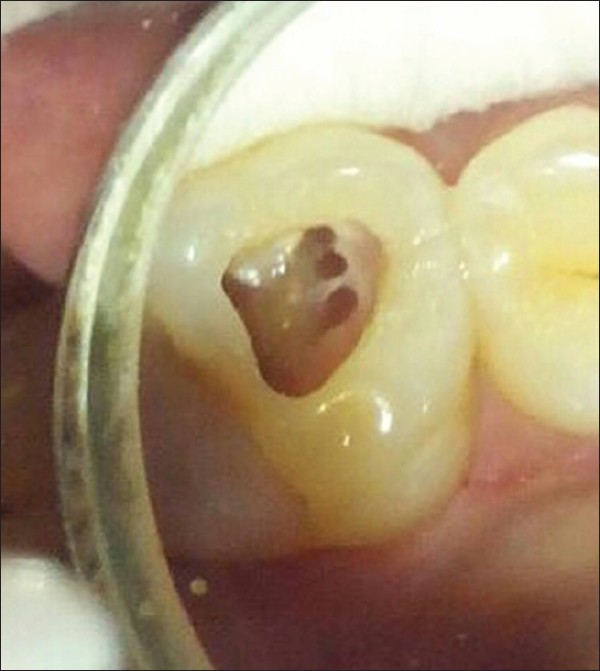

Management of C-shaped root canal configuration with three different obturation systems  |

Deenadayalan Elumalai, Ashok Kumar, Rajendra Kumar Tewari, Surendra Kumar Mishra, Syed Mukhtar-Un-Nisar Andrabi, Huma Iftekhar, Sharique Alam DOI:10.4103/2278-9626.149685 Unusual root canal anatomy always poses a diagnostic and treatment challenge. Identification of such variation is important for the success of the root canal treatment outcome. The C-shaped root canal configuration is one of the aberrant morphology of molar teeth, commonly the mandibular second molar. In this configuration, the canals are connected by slit or web. The presence of fin, slit and web makes through debridement obstacle for the clinician. This case reports present successful management of C-shaped mandibular molars with three different obturation systems. |